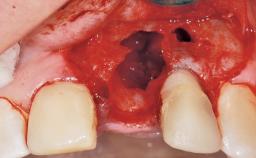

Early Placement of an Implant in a Maxillary Right Central Incisor Site

Bone Volume Horizontally and vertically sufficient Horizontally deficient Deficient vertically or deficient vertically AND horizontally

Bone Volume Deficient horizontally, allowing simultaneous augumentation